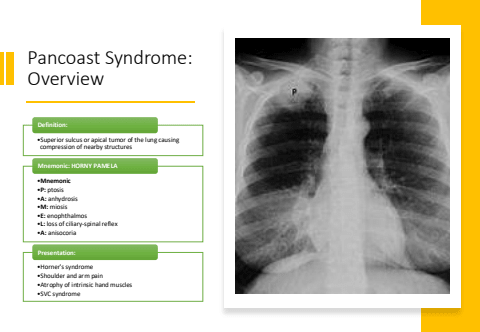

Pancoast Syndrome: Overview%u2022Superior sulcus or apical tumor of the lung causing compression of nearby structuresDefinition:%u2022Mnemonic%u2022P: ptosis%u2022A: anhydrosis%u2022M: miosis%u2022E: enophthalmos%u2022L: loss of ciliary-spinal reflex%u2022A: anisocoriaMnemonic: HORNY PAMELA%u2022Horner's syndrome%u2022Shoulder and arm pain%u2022Atrophy of intrinsic hand muscles%u2022SVC syndromePresentation: